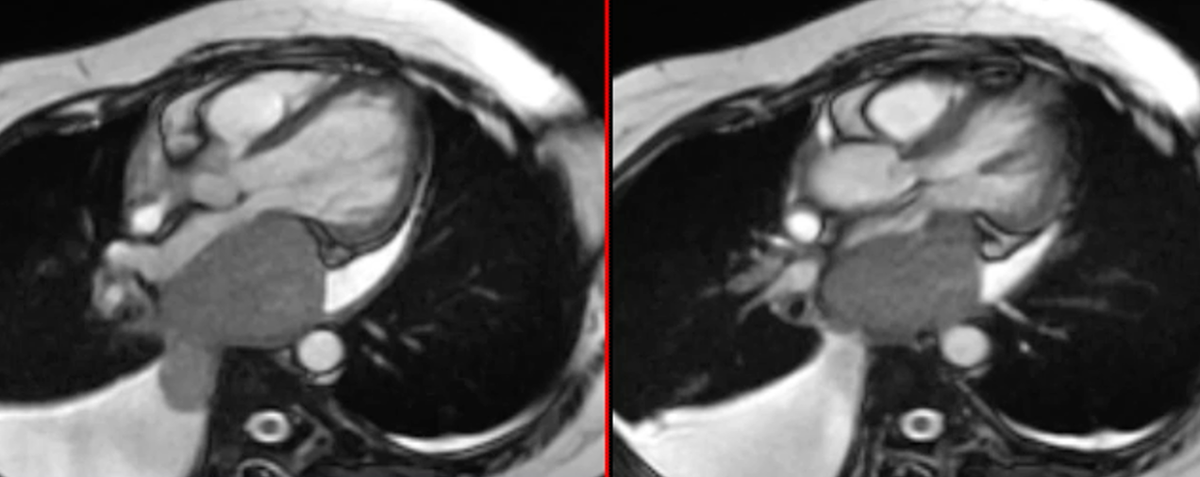

Rare extracardiac mass